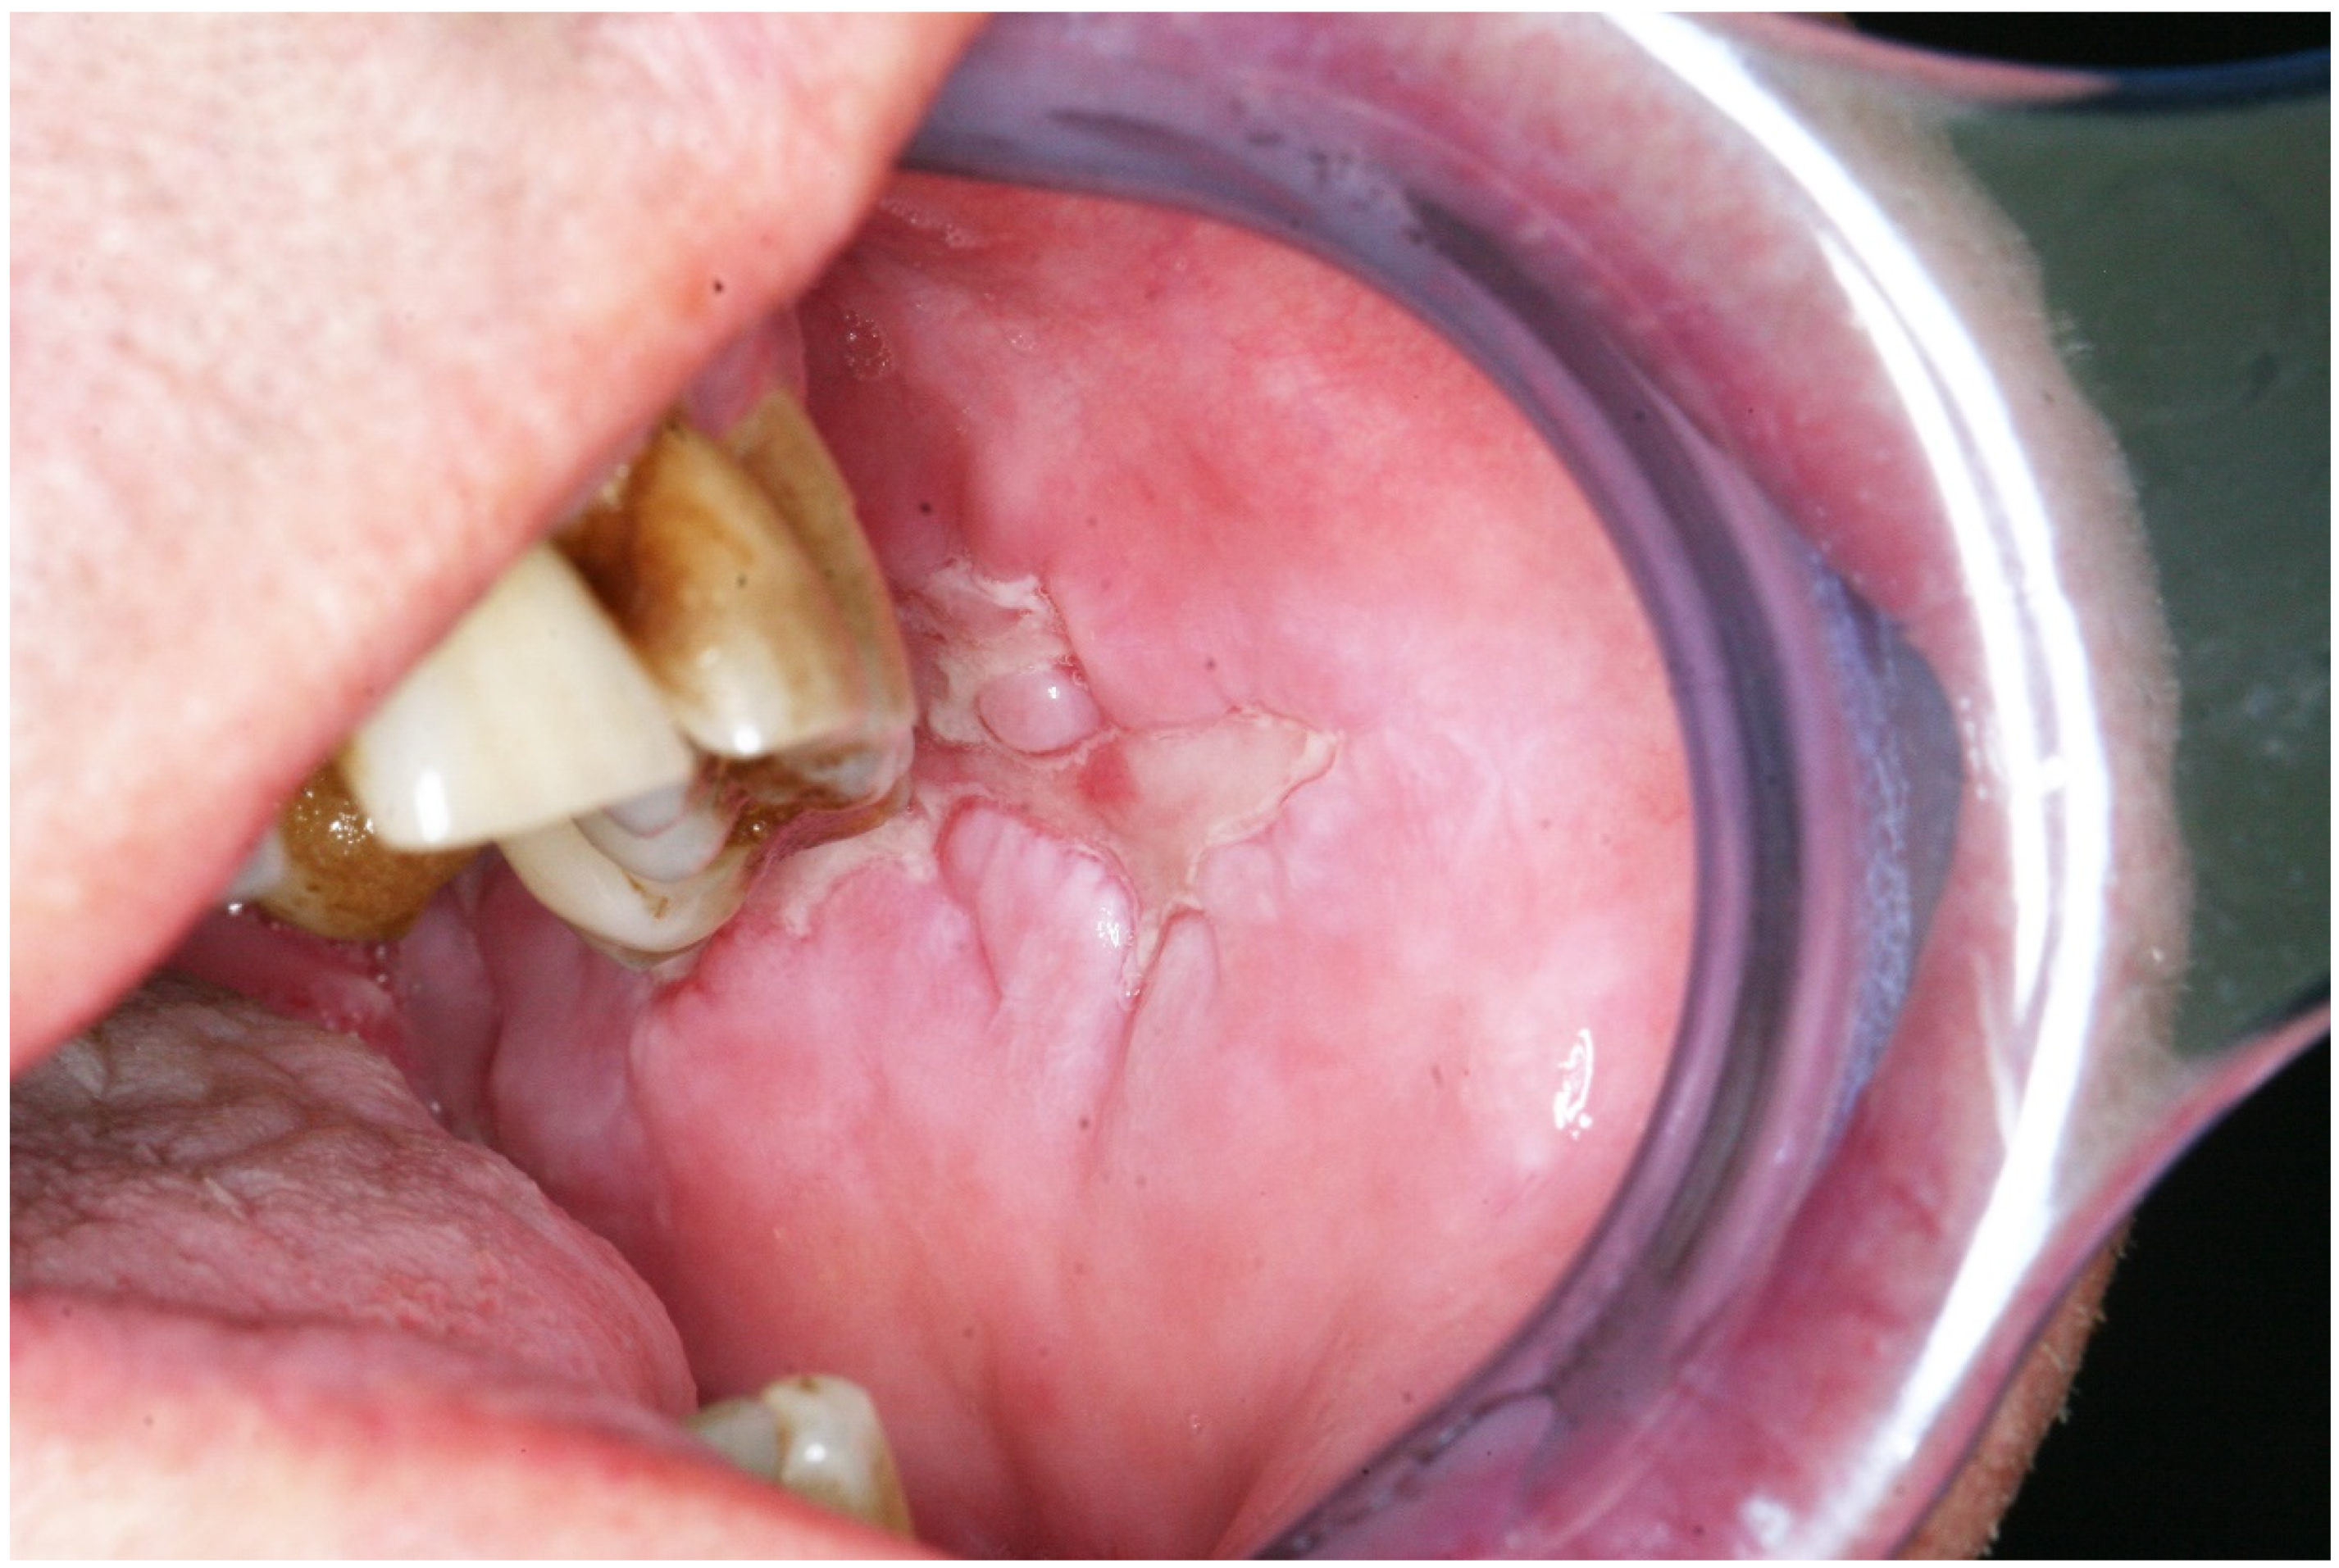

PNP is characterized by polymorphous lesions, involving the skin and different mucosae. The variety of lesions could be explained by the different subsets of auto-Ab that could be detected in different patients [7,11]. Mucosal lesions are usually the earliest features in PNP [7,11]. Oral mucosa is always affected in PNP (Figure 3) [7,11]. Usually, severe erosions involve the vermilion of the lips and the oropharynx, causing a painful stomatitis. Mucosal lesions can also involve the nasopharynx, conjunctivae, anogenital region, and esophagus [7,11]. Cutaneous lesions usually rise after the onset of mucosal ones [7,11]. Different lesions may coexist and evolve from one type to another. Cutaneous lesions could be similar to those seen in pemphigus, pemphigoid, erythema multiforme, and graft versus host disease [7,11]. In addition, pustular and psoriasis-like lesions have been described [8]. The different clinical features could be linked to the predominance of the cell-mediated or humoral-mediated cytotoxicity [7,11,26]. Indeed, it has been reported that pemphigus lesions are prominent when the main underlying pathogenetic mechanism is the humoral-mediated cytotoxicity [7,11]. In contrast, if cell-mediated cytotoxicity is the leading pathogenetic mechanism, lichenoid lesions might be easily seen [22,25]. Lichenoid lesions are more commonly detected in children, especially on the trunk and limbs (Figure 4) [12]. PNP can also involve the respiratory epithelium in up to 92% of cases, causing dyspnea, obstructive lung disease, and bronchiolitis obliterans (BO) [7,11].

Figure 3.

Paraneoplastic pemphigus (oral lesion). Obligate paraneoplastic dermatosis characterized by painful mouth ulcerations. It is usually associated with myeloproliferative and lymphoproliferative disorders.